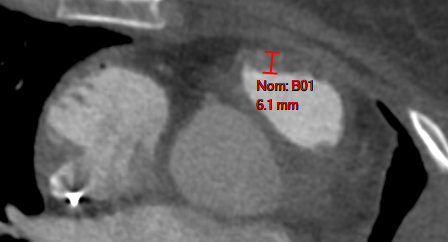

Signes Cardio-Vasculaires d’HTAP

- Epaississement du VD (Paroi libre >5mm et Infundibulum)